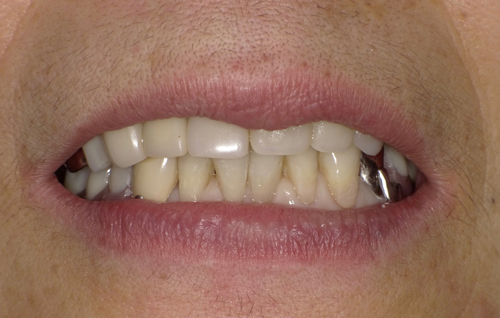

大阪市内より20代の女性。主訴は「2ヶ月前、左下の歯を抜いた。麻酔が効いていないのに抜歯を続けられた。

歯のない所はインプラントにしようと思っている。前歯も綺麗にしたい。痛みや怖いのはゴメンなので、静脈麻酔鎮静で治療をしてもらいたい。」でした。

適合の良くなかった前歯もセレックを使って、オールセラミックスに順次やり変え。

患者様「想像以上に綺麗になって嬉しい。インプラントの2本も本当に違和感なくよく噛める。